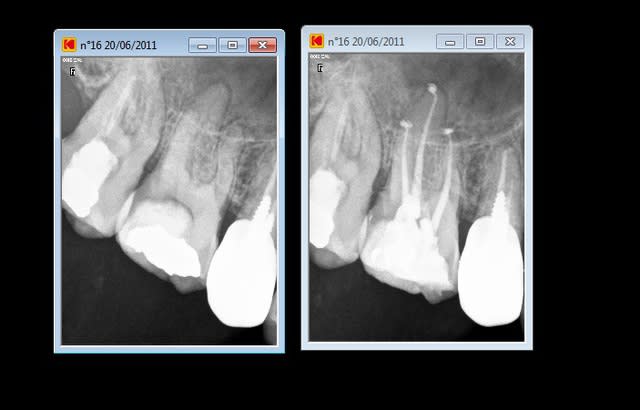

Bon...on va attendre 6 mois avant de dire qu'il n'y a pas de soucis. La difficulté ici était le lentulo fracturé coronairement qui n'autorisait pas le by-pass (au départ, parce que je lui ai expliqué qu'il fallait qu'il se pousse pour me laisser passer et il a été gentil, il m'a obéit :-))

En fait, ça ne se voit pas sur la radio d'eugenol (perte de qualité) mais il y a un lentulo dans l'obturation du canal MV (et un autre au niveau apical que l'on voit ici).

Pour répondre à dumaille : oui. Si tu regardes bien la radio postop, tu verras des trabécules osseuses juste sous la furcation. Le sondage était normal aussi bien en lingual qu'en vestibulaire. La lésion étant fermée, il n'y a aucune raison qu'en cas de succès apical il y ait une persistance radioclaire entre les racines.

Pour Aymen : Une fois le by-pass réalisé, Dominique Martin conseillait il y a quelques années dans une conférence de la SOP de rester en manuel avec les instruments NiTi. Je ne sais pas s'il s'applique ça à lui même ou si c'était un conseil destiné aux praticiens lambdas. Personnellement, je prend souvent ce risque (si je sens intuitivement en fonction du cas que je peux le faire, et si j'ai le moindre doute, je pense à mon ami Willy qui me disait un jour "si tu te poses la question, ne le fais pas !" Je pense d'ailleurs souvent à lui à cause de ça car il y a plein de situations cliniques où je me pose des questions. Dans le cas présenté, j'y suis allé en rotation mécanique justement. L'instrument fracturé coronairement à été enlevé après la mise en forme. Il faut bien comprendre qu'ici, ce fragment était un lentulo. Si ça avait été un protaper F2 par exemple, je serai sans doute rester en manuel, en fonction des sensations tactiles avec le dernier instrument acier utilisé (ici une lime K15).

Pour l'obturation, je ne vois aucune raison de changer quoique ce soit à cause d'un fragment d'instrument qui resterait en place. Une technique à chaud me parait cependant idéale pour enrober le fragment. Dans le cas présent, c'était thermafil et la courbure apicale en était une excellente indication à mon avis.